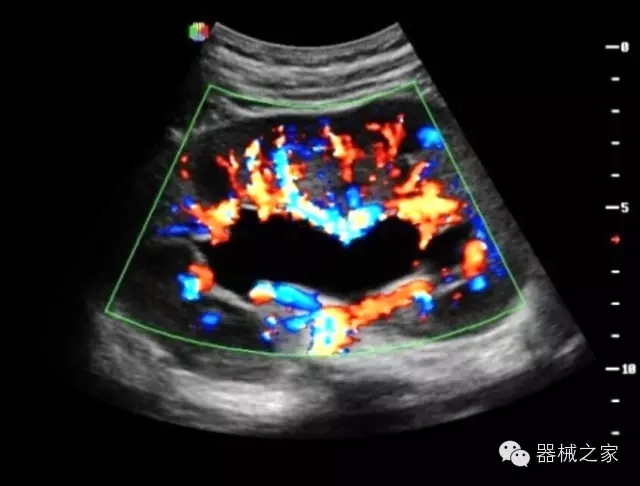

經(jīng)典產(chǎn)品:S8EXP

臨床圖片賞析

產(chǎn)品特點(diǎn)